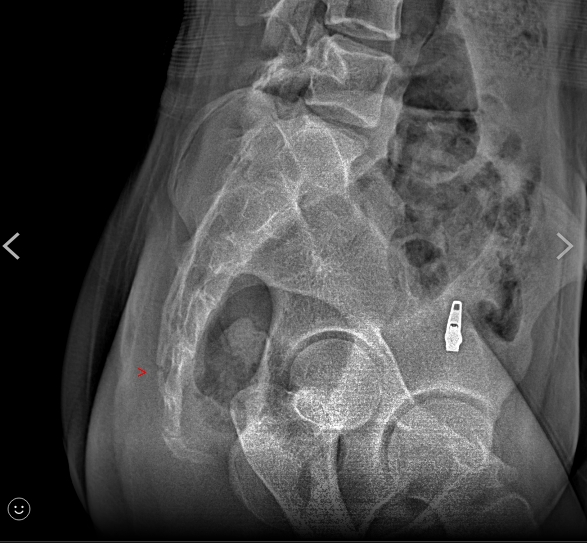

「她是這個地方裂了!」秀出X光片,還有受傷照,表面明顯瘀青,診斷證明書寫著,臀部挫傷,尾骨骨折,讓家長一看超心疼,要調閱監視器、釐清真相,但從11月25號發生至今,已經7天,學校遲遲沒有回應。不過校方祭出4點聲明說,練習場地在藝文中心舞台上,地板材質是礦石卡扣地板,有彈性,鋪防護墊容易滑,反而造成抬舉的學生受到更嚴重的傷害,才沒有使用防護墊,後續會尋覓合適場地,也會避免做抬舉動作,對於學生受傷,表達遺憾。